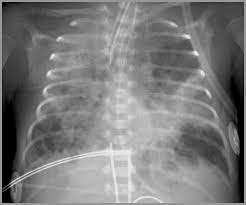

Mε σπάνιες εξαιρέσεις η ΒΠΔ παρατηρείτιαι σε πρόωρα νεογνά, τα οποία υποχρεώθηκαν να δεχθούν παρατεταμένης διάρκειας μηχανικό αερισμό. Τα ακτινολογικά ευρήματα περιλαμβάνουν υπερέκπτυξη και ανομοιογένεια του πνεύμονος, με λεπτές και αδρές σκιάσεις που εκτείνονται προς την περιφέρεια, στις σοβαρότερες περιπτώσεις. Σε ηπιότερες περιπτώσεις, οι ακτινολογικές μεταβολές είναι, επίσης, ηπιότερες, καθώς εμφανίζονται, εν γένει, διάχυτες σκιάσεις. Οι βλάβες αυτές επιβάλλουν τη συνέχιση του μηχανικού αερισμού και εμπλουτισμένα μίγματα οξυγόνου γγια μήνες κια, ενδεχομένως, χρόνια. Λόγω της μετεμβρυϊκής χορηγήσεως κορτικοειδών και εξωγενούς επιφανειοδρατικής ουσίας, πολλά πρόωρα χρειάζονται επίσης μηχανικό αερισμό με χαμηλές πιέσεις και συμπληρωματικό οξυγόνο. Μετά μερικές ημέρες ή ρβδομάδες εφαρμογής μηχανικούα αερισμού, τα νεογνά εμφανίζουν προοδευτική επιδείνωση της αναπνευστικής λειτουργίας και αύξηση των απαιτήσεων σε μηχανικό αερισμό και οξυγόνο, ενώ εμαφανίζονται σημεία αναπνευστικής ανεπάρκειας, ώσπου τελικά, εμφανίζουν ΒΠΔ. Η επιδείνωση αυτή πυροδοτείται συχνά από βακτηριακές ή ιογενείς λοιμώξεις, δευτεροπαθείς με ανοικτό βωτάλειο πόρο. Τα νεογνά που επιβιώνουν εμφανίζουν προοδευτική βελτίωση της αναπνευστικής τους λειτουργίας και των ακτινολογικών ευρημάτων, με προοδευτικό απογαλακτιχμό από τον μηχανικό αερισμό και τη χορήγηση συμπληρωματικού οξυγόνου. Σημειώνεται ότι συχνά, μετά την αποσωλήνωση επιμένουν για διάστημα ευρήματα αναπνευστικής δυσχέρειας, όπως ταχύπνοια και εισολκή του θωρακικού τοιχώματος (δείγμα κοπιώδους αναπνοής). Οι περισσότερες σοβαρές περιπτώσεις ΒΠΔ μπορεί να εξελιχθούν σε αναπνευστική ανεπάρκεια, ακόμη και μέδρι το θάνατο, ως αποτέλεσμα σοβαρής πνευμονικής βλάβης και πνευμονικής υπετάσεως και αλλεπάλληλων λοιμώξεων. Μερικά από τα νεογνά αυτά μπορεί, ακόμη, να αναπτύξουν αναστομώσεις μεταξύ στηματικής και και πνευμονικής κυκλοφορίας, με αποτέλεσμα την επιδείνωση της πνευμονικής υπερτάσεως. Οι οξείες πνευμονικέ ςλοιμώξεις -βακτηρικές ή ιογενείς- συνήθως επιπλέκουν σοβαρά την πορεία της ΒΠΔ και, σε πολλές περιπτώσεις είναι ο επισπε΄θυδων απράγοντας στο θάνατο. Λόγω της χρόνιας υποξίας και της μεγαλύτερης καταναλώσεως οξυγόνου, εκ της κοπιώδους αναπνοής και του αυξημένου έργου αναπνοής, η ανάπτυξη των νεογνών αυτών υπολείπεται του φυσιολογικού ακόμη και ένα λαμβάνουν τον απαιτούμενο, για την ηλικία τους αριθμό θερμίδων, ημερησίως. Επιπλέον, η ελλιπής ανοχή στη διατροφή και η τάση για κατακράτηση υγρών και ανάπτυξη πνευμονικού οιδήματος, συνήθως απαιτεί περιορισμό ύδατος όπως καιθεραπεία με διουρητικά, με αποτέλεσαμ την περαιτέρω μείωση των προσλαμβανόμενων θερμίδων.